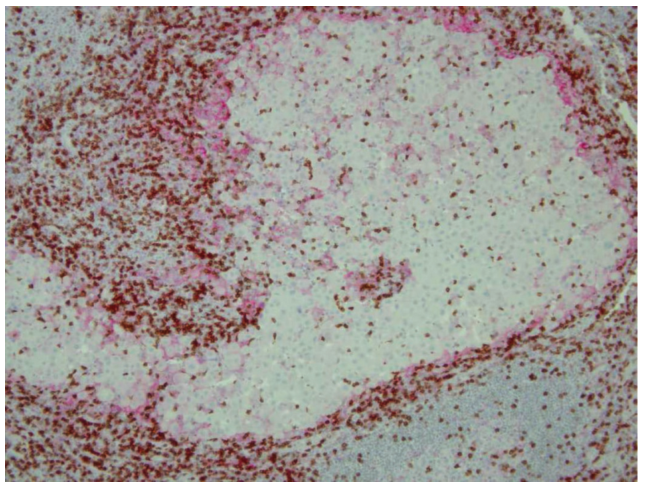

在表面TCR与携带黑色素瘤抗原肽的MHC-I复合物结合后,黑色素瘤特异性CD8+T细胞被激活,随后释放干扰素γ,诱导周围黑色素瘤细胞表达PD-L1(也称为B7-H1和CD274),如Fig. 19.1所示。PD-L1与CD8+T细胞上的抑制性共受体PD-1结合,从而削弱T细胞的效应器功能(细胞溶解颗粒和细胞因子释放),抑制其增殖。此外,PD-1还能与PD-L2结合,但是在黑色素瘤细胞上检测不到这种结合。正常情况下,T细胞中的PD-1信号对机体维持自身免疫耐受具有重要意义,PD-1基因敲除小鼠出现自发的自身免疫反应证明了这一点。因此,PD-1是抑制CD8+T细胞功能的重要检查点,黑色素瘤细胞通过表达PD-L1,获得了直接降低T细胞活性的能力(Fig. 19.2)。而在从肿瘤组织和黑色素瘤患者外周血中分离出的新抗原特异性CD8+T细胞上,也发现了PD-1的表达,这为开发阻断PD-1和PD-L1之间相互作用的治疗策略提供了理论基础(Fig. 19.2)。

Fig. 19.1 CD8+T细胞旁边的黑色素瘤细胞表达PD-L1。通过免疫组化染色标记黑色素瘤淋巴结病变中的CD8+T细胞(棕色)和黑色素瘤细胞(PD-L1, 红色)。